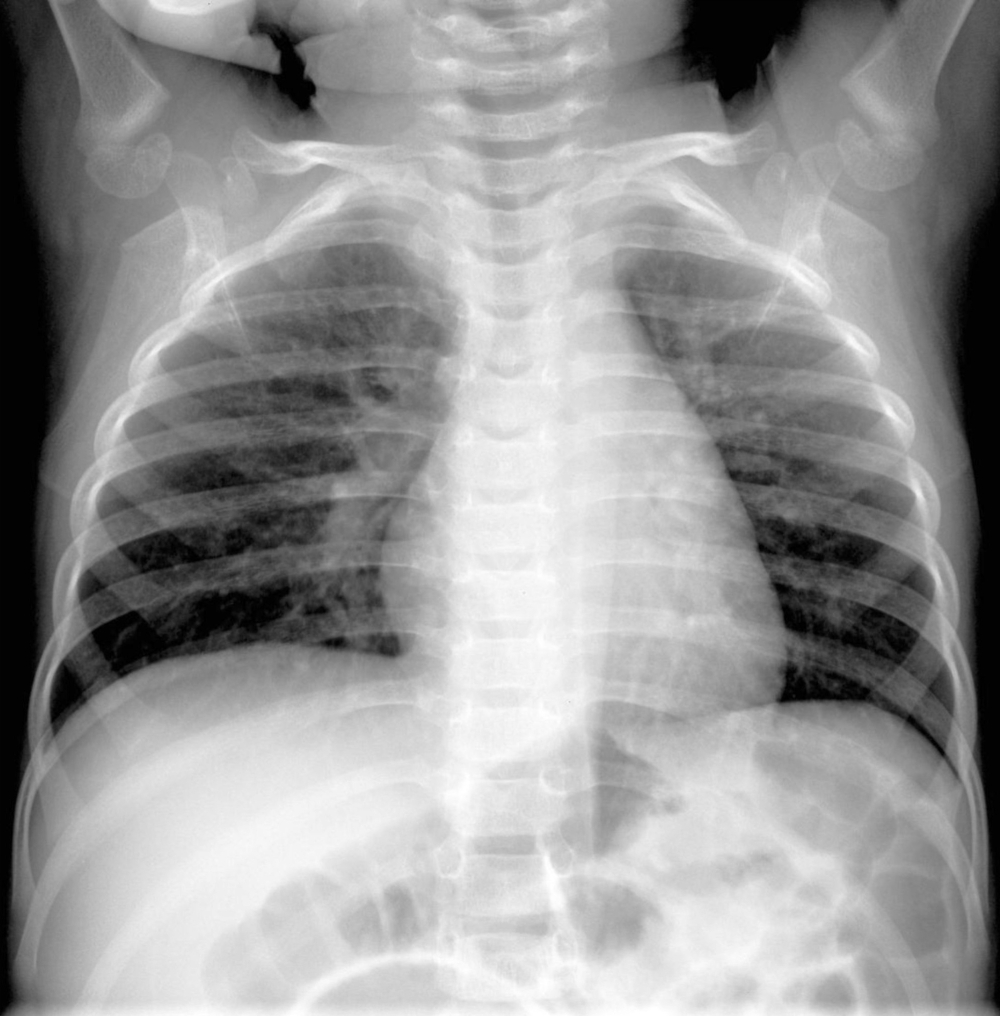

Most HMPV infections are mild, resembling bouts of the common cold. However severe cases can result in bronchitis or pneumonia, particularly among infants, older adults, and immunocompromised people. Patients with preexisting lung conditions, such as asthma, chronic obstructive pulmonary disease, or emphysema, are at higher risk of severe outcomes.